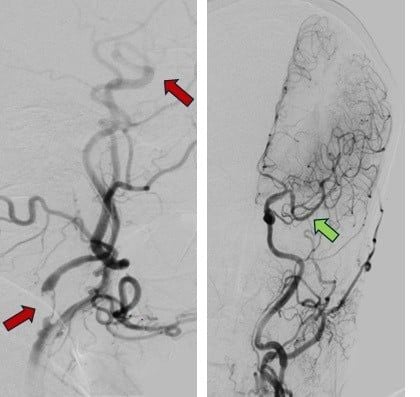

Hình ảnh mạch máu bị tắc (mũi tên đỏ) và sau khi được tái thông hoàn toàn (mũi tên xanh) (ảnh: BV)

Quy trình can thiệp bắt đầu lúc 9 giờ 45 phút. Ekip đưa ống thông siêu nhỏ từ động mạch đùi lên tới vị trí tắc, lấy thành công cục máu đông chỉ sau 55 phút. Hình ảnh chụp mạch cho thấy dòng máu đã được tái thông hoàn toàn (TICI 3).